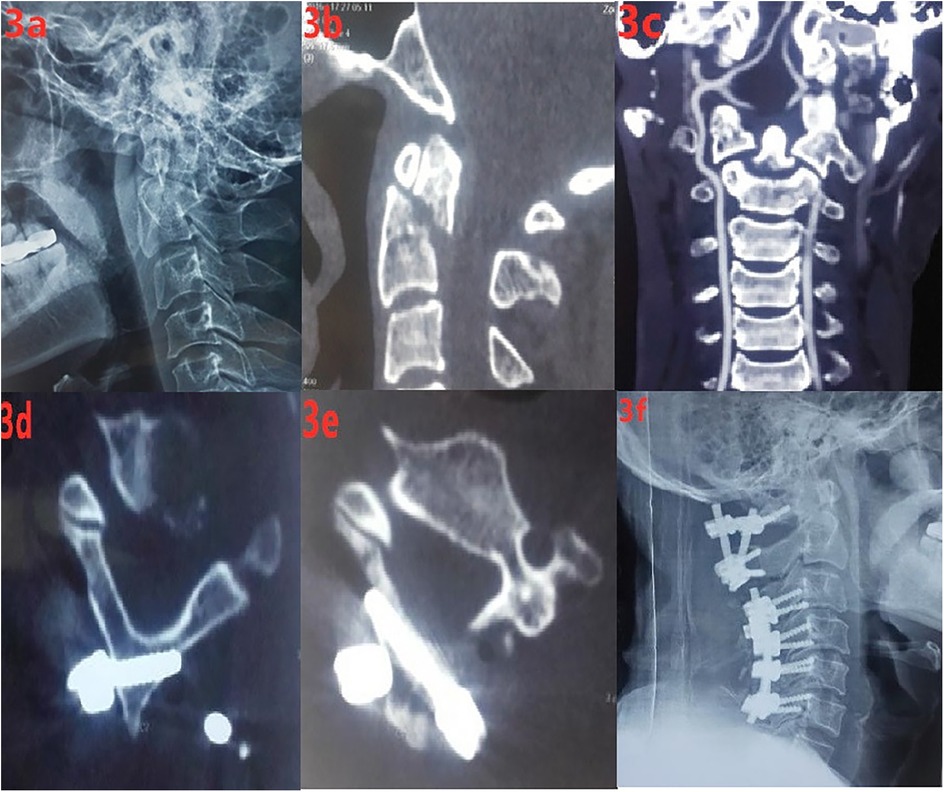

A 47-year-old male patient sustained an upper cervical spine injury due to a traffic accident. After x-ray and CT examinations were completed, the diagnosis was (1) Odontoid process fracture (Anderson type II), (2) Cervical spinal cord hyperextension injury (Frankel D), and (3) Cervical canal stenosis. Posterior open reduction, bone grafting, fusion, and internal fixation with bicortical laminar screws were planned for the odontoid process fracture. Below is the detailed information of the case (Figures 3A–F).

Six-panel medical imaging series displaying various stages of cervical spine examination and surgery. Panel 3a shows a lateral X-ray of the cervical spine. Panels 3b and 3c display CT scans of the cervical vertebrae. Panel 3d and 3e depict close-up CT images focusing on specific vertebra structures. Panel 3f shows a post-surgery X-ray with metal screws and plates stabilizing the spine.

Figure 3. (a) preoperative cervical lateral x-ray; (b,c) preoperative cervical spine CT; (d,e) postoperative CT showing that the C2 laminar screws were in good position and did not protrude into the spinal canal; (f) postoperative lateral x-ray of the cervical spine.